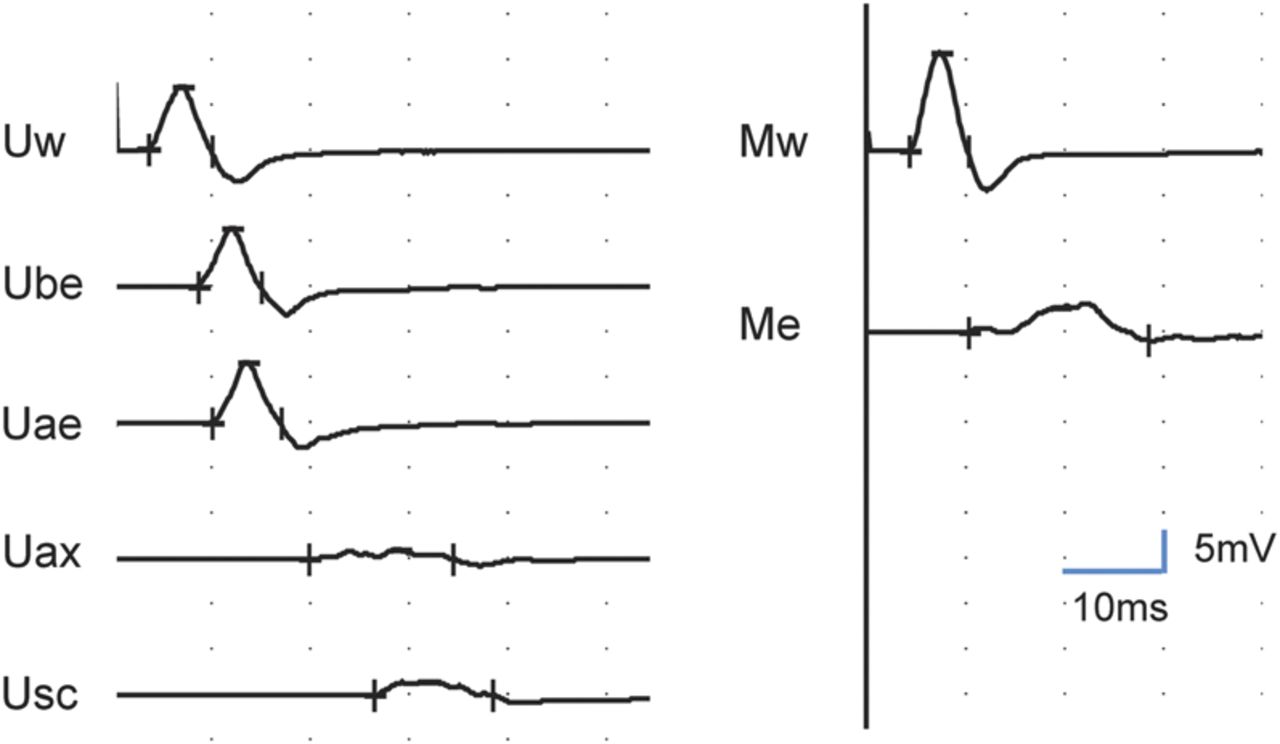

一位68岁的男子抱怨多年来左臂不协调、虚弱。临床检查显示假性震颤和轻微的左臂整体无力,袜子模式振动和针刺不敏感,只有轻微的左手本体感觉障碍首页®网址:首页Neurology.org).神经传导研究显示感觉电位普遍缺失或严重减弱,上肢多处运动传导阻滞(图1).MRI显示左臂丛神经根及干不对称扩大(图2).慢性炎性脱髓鞘性多神经根神经病可引起震颤,1但多灶性获得性脱髓鞘感觉和运动神经病,2不对称形式,尚未报道引起假手足徐动症。

图1

尺正中运动神经传导

正中和尺侧运动传导阻滞分别刺激肘关节和腋窝。Ae =肘部以上;Ax =腋窝;在肘部以下;E =肘;M =中位数;Sc =锁骨上;U =尺骨;W =手腕。